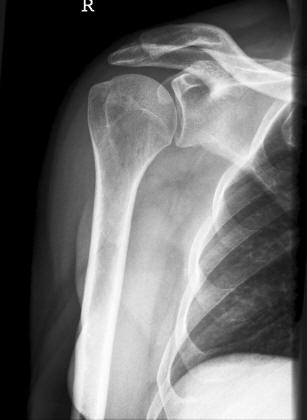

Schulter a.p.

Fehler

Hier erfolgte eine ungenügende Rotation in der Schulter, so dass das Gelenk nicht frei dargestellt wurde.

Abhilfe

Abhilfe bringt eine weitere Drehung des Patienten nach dorsal.